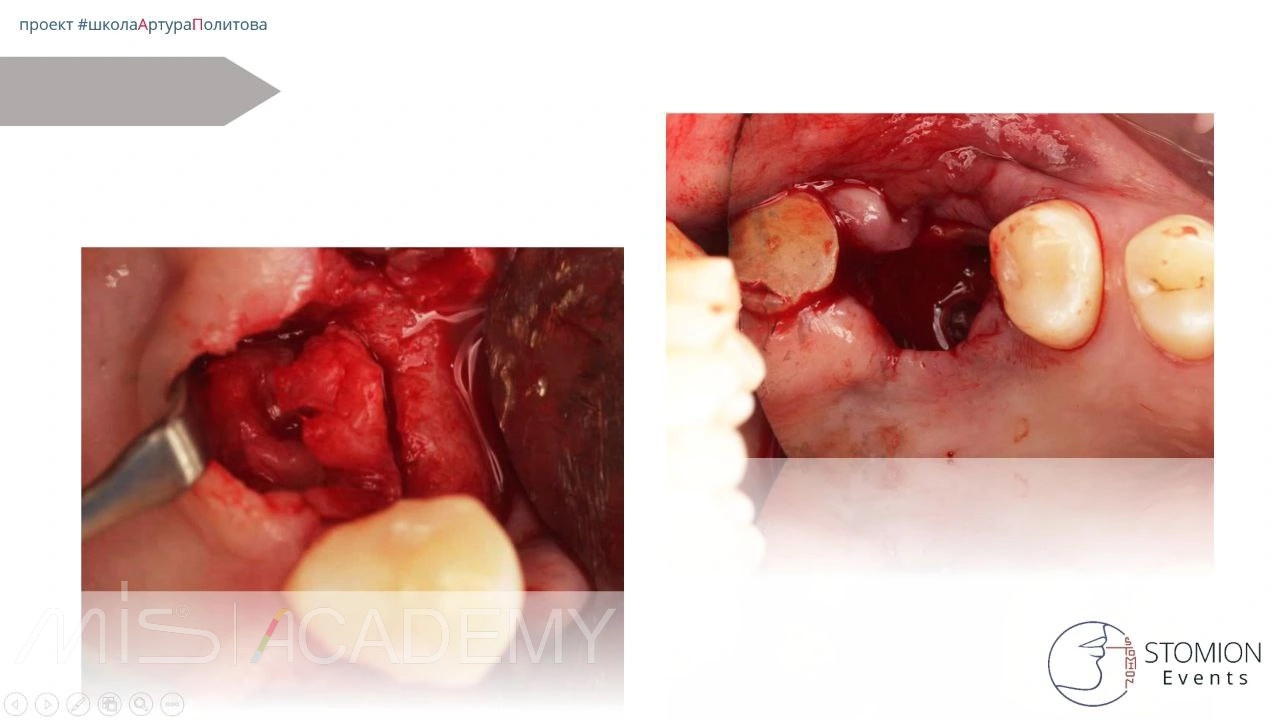

Хирургический этап:

• Выполнено расщепление лоскута.

• Проведён транскрестальный синус-лифтинг.

• В субантральное пространство внесён Коллапол.

• Одновременно удалён зуб 4.8, трансплантирован в область адентии 1.6 с ТКСЛ.